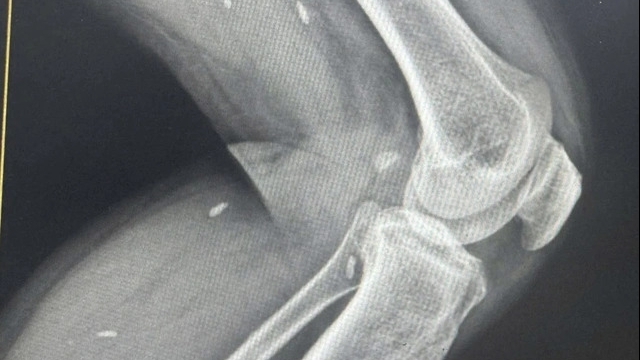

Một nghiên cứu đã được tiến hành tại Hàn Quốc về mối liên quan giữa virus corona và bệnh viêm phổi ở những người nhập viện từ 18 đến 39 tuổi. Tại Hàn Quốc, tất cả những người nhiễm virus đều phải nhập viện một cách có hệ thống (trong giới hạn số giường có sẵn), tức là bao gồm cả những người mắc COVID-19 thể nặng hay thể nhẹ, cũng như những người không có triệu chứng.

Kết quả cho thấy, trong số 315 người nhập viện, ít nhất 83 trường hợp (26%) bị viêm phổi, trong đó 7 ca nghiêm trọng. Các nhà nghiên cứu kết luận, những người trẻ cũng cần phải ý thức về nguy cơ viêm phổi, thậm chí là viêm phổi nặng do COVID-19.